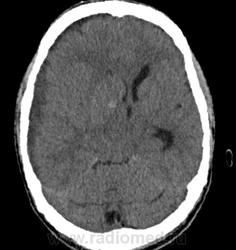

Обратите внимание на субдуральное пространство справа. Определяется тонкое пластинчатое скопление патологического изоденсного содержимого над конвекситальными отделми правой гемисферы большого мозга. Слева оболочечные пространства выражены обычно.

Каюсь, я так сосредоточилась на костных изменениях, что факт наличия этого содержимого в третьем часу ночи был мной упущен.

Была произведена фронтотомия, эвакуировано гнойное содержимое. Пациент в сознании, актвен, был госпитализирован в ЛОР-отделение. Через 3 дня клиническое ухудшение состояния, сопор. Выполнено контрольное КТ головного мозга с контрастным усилением.